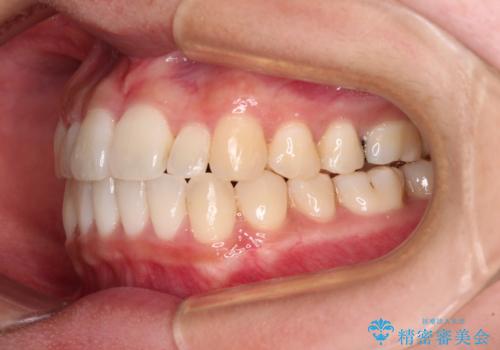

すきっ歯とオープンバイトをインビザラインで改善

- 前歯の上下スペースと前歯の隙間を気にして来院された患者様です。

インビザラインにより上下の前歯の隙間を閉じていくこととしました。

上下の隙間に舌が入り込むことが、すきっ歯やオープンバイトの原因であったため、舌の筋肉のトレーニングも並行して行い、後戻りの抑制を図りました。